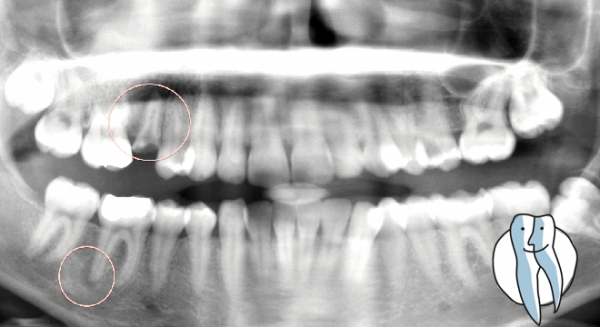

Der abgestorbene Zahn fällt auch nicht zwangsläufig aus, häufig merkt der Betroffene gar nichts am Zahn. Es kommt zu einer leichten Aufbissempfindlichkeit, zu einer gesteigerten Heiss/Kalt-Empfindlichkeit. Unser Tipp ist daher, auch bei leichten Beschwerden diesen Zahn kontrollieren zu lassen. Oft bringt ein Röntgenbild eine Entzündung an der Wurzelspitze zutage.